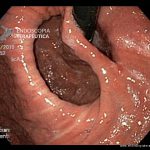

Hérnia hiatal paraesofágica

- Hérnia hiatal paraesofágica e fundoplicatura parcialmente desgarrada